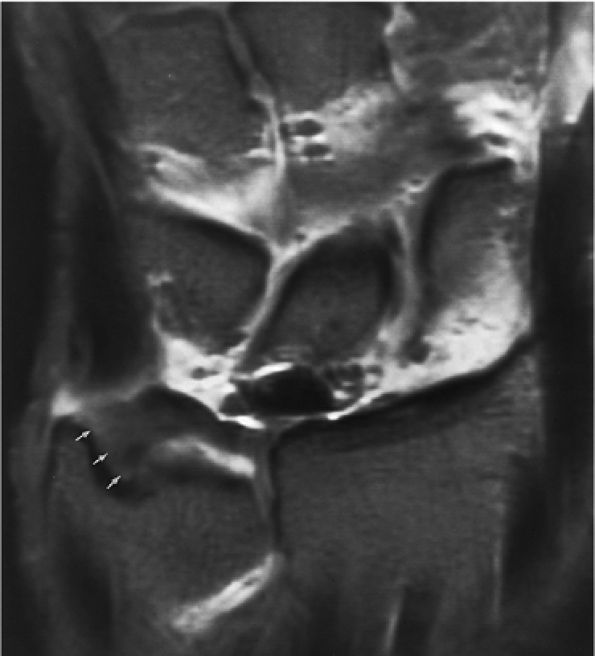

-

The scapholunate ligament is triangular on coronal section and is peripherally attached at the scapholunate interval. The inner apex of the triangular ligament is not attached to bone and is free within the scapholunate joint (Fig. 10.74).52

The dorsal fibers of the scapholunate ligament are oriented transversely, or perpendicular to the joint, and form a thick bundle. The dorsal portion of the scapho-lunate ligament is considered to be the most important component in maintaining carpal stability.

The membranous scapholunate ligament fibers course peripherally and obliquely from the scaphoid downward to the lunate. The membranous scapholunate ligament fibers attach to both bone and articular cartilage, whereas the dorsal and volar portions of the scapholunate ligament attach directly to bone.

The volar scapholunate ligament fibers course obliquely between the volar aspects of the lunate and scaphoid.

The lunotriquetral ligament is usually visualized as a thin horseshoe-shaped structure that may appear more lax than the scapholunate ligament on MR imaging.43 The lunotriquetral ligament does not extend as far distally into the lunotriquetral joint as the longer proximal distal portion of the scapholunate ligament does within the scapholunate joint.

The volar and dorsal portions of the lunotriquetral ligament attach directly to bone, whereas its midportion attaches to the hyaline articular cartilage of the lunotriquetral joint.43

Smith and Snearly53 have shown that on coronal MR images the lunotriquetral ligament is most commonly delta-shaped (triangular) or linear.